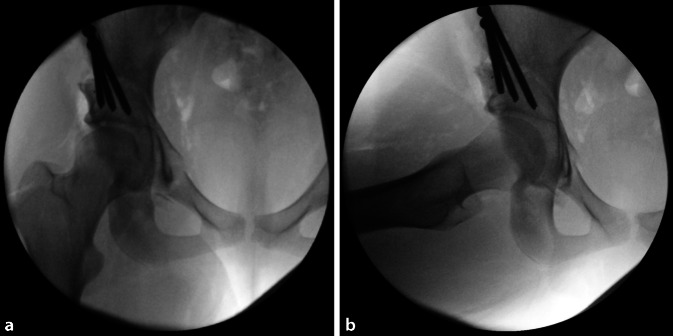

(Abb. 3, 4, 5, 6, 7, 8, 9, 10, 11, 12, 13, 14, 15, 16 und 17).

Gefahr von intraazetabulären Frakturen: Die intraoperative Durchleuchtung ist obligat, um Komplikationen bei der Durchführung einer PAO zu vermeiden. Insbesondere hat sich die Durchleuchtung als zuverlässiges diagnostisches Werkzeug zur Vermeidung von Verletzungen der hinteren Säule und intraartikulärer Osteotomien erwiesen.